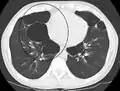

انجام رادیوگرافی قفسه سینه و شمارش کامل خون ممکن است در زمان تشخیص، احتمال ابتلا به شرایط دیگر را از میان بردارد.[49] نشانههای مخصوص در رادیوگرافی شامل گشاد شدن ششها، دیافراگم صاف، فضای خالی افزایش یافته پشت جناغ و آبکیسه میباشد، این در حالی است که میتواند بیماریهای ریوی دیگر مانند سینهپهلو، اِدِم ریه یا پنوموتوراکس را شامل نشود.[50] اسکن رزلوشن بالای توموگرافی رایانهای از سینه ممکن است پخش آمفیزم در ریه را نشان دهد و میتواند احتمال ابتلا به بیماریهای ریوی دیگر را از میان بردارد.[2] این مورد، غیر از مواقعی که عمل جراحی انجام شدهاست، به ندرت بر مدیریت بیماری تأثیر میگذارد. فشار گاز خون شریانی برای تعیین نیاز به اکسیژن استفاده میشود و برای افرادی که FEV1 آنها کمتر از ۳۵٪ پیشبینی شدهاست، افرادی که اشباع اکسیژن خون آنها کمتر از ۹۲٪ است و افرادی که علائم نارسایی احتقانی قلبی دارند توصیه میشود. در مناطقی از جهان که نقص آنتی تریپسین آلفا-۱ شایع است، باید از افراد دچار COPD (مخصوصاً افراد زیر ۴۵ سال که آمفیزم روی قسمتهای تحتانی ریههایشان اثر گذاشتهاست) آزمایش گرفته شود.[8]

Chest X-ray demonstrating severe COPD. Note the small heart size in comparison to the lungs.

A lateral chest x-ray of a person with emphysema. Note the barrel chest and flat diaphragm.

Lung bulla as seen on CXR in a person with severe COPD

A severe case of bullous emphysema

Axial CT image of the lung of a person with end-stage bullous emphysema.